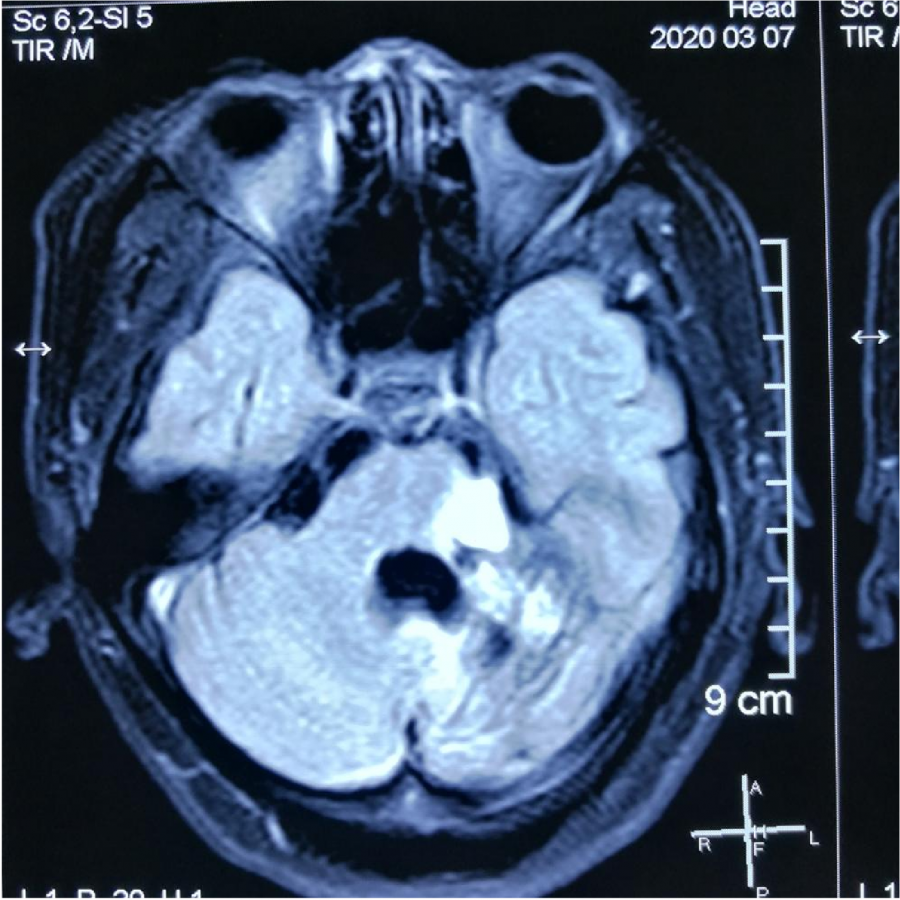

⼊院CT显⽰:桥脑旁有出⾎

MR显⽰桥脑左侧⾼信号影

小脑及脑⼲受累